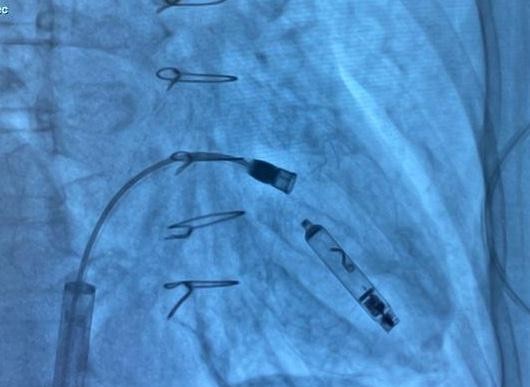

Under fluoroscopic guidance, the delivery catheter was advanced through the right atrium. Significant resistance was encountered as the catheter tip repeatedly abutted the ventricular wall due to the limited chamber size. To overcome this, the catheter was reshaped into a “hockey-stick” configuration developed by our team (Fig. 4–9). This modification enabled safe passage through the tricuspid valve and facilitated navigation to the apical-septal region. Contact mapping confirmed optimal electrical parameters before fixation, and the device was screwed into the septum. Device interrogation demonstrated proper function: pacing threshold 0.75 V at 0.4 ms, R- wave amplitude 6.0 mV, impedance 750 Ω, mode VVI, with estimated battery longevity of ~12 years.

Figure 5. Implantation phase of the pacemaker

Figure 6. Fluoroscopic image showing the Aveir™ VR leadless pacemaker positioned in the right ventricular septum

At the junction of the superior vena cava and right atrium, maximal deflection of the distal catheter segment was applied, followed by slight retraction, creating an acute 70–90° bend resembling a “hockey stick.” This configuration shortened the working length, allowing maneuverability in the restricted RV cavity. Crossing the tricuspid valve was guided by RAO 30° and LAO 40° projections to ensure septal alignment. In the apical-septal region, contact mapping (with the helix unreleased) confirmed acceptable parameters (R-wave ≥5 mV, threshold ≤1.0 V at 0.4 ms, impedance 400– 1500 Ω). Upon satisfactory values, the device was screwed into the septum with 1.5 turns. Perpendicular positioning was confirmed in orthogonal views, followed by a tug test. Repositioning was feasible if parameters were suboptimal.